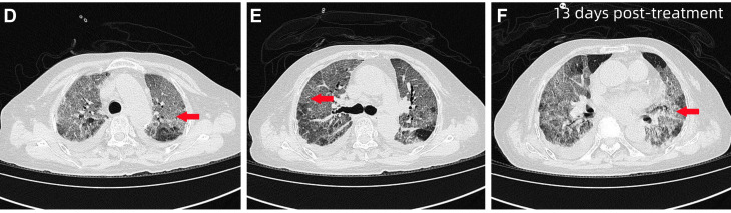

图2 患者住院第13天HRCT 图像,显示双肺弥漫性磨玻璃影伴部分实变(红色箭头),以双肺下叶为主,可见局部空气支气管征及双侧胸腔积液(右侧更为明显)